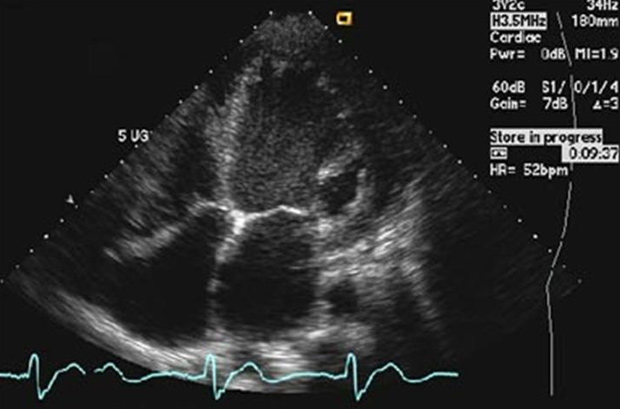

Cada coração tem sua cadência, mas alterações bruscas podem levar à morte